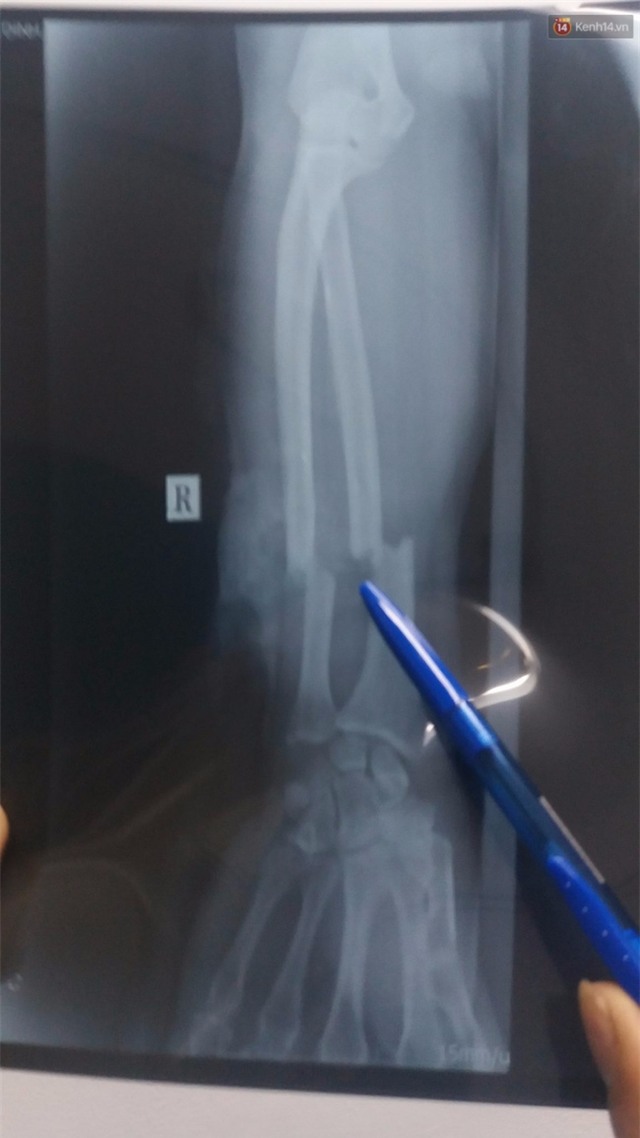

Cánh tay nạn nhân bị chém đứa lìa xương. |

Nạn nhân đưa vào viện trong tình trạng mất máu nhiều, vẫn còn tỉnh táo. Sợ nạn nhân có thể tử vong do mất máu, sốc hoặc vết thương quá đau đớn, các y bác sĩ đã cầm máu, hồi sức và đưa bệnh nhân vào phòng để thực hiện nối cơ, xương, thần kinh cho tay bệnh nhân. Ngoài vết chém gần đứt lìa ở cẳng tay phải, nạn nhân còn bị lộ xương bánh chè gối trái, đứt phần cơ rộng đùi trái.

Bác sĩ Hà cho biết: "Phía bệnh viện đã dùng phương pháp vi phẫu thuật (nối thần kinh, mạch máu, gân kết hợp xương), đến giờ bệnh nhân tỉnh táo, sinh hiệu ổn. Hiện tại, nạn nhân được chăm sóc ở phòng vô trùng, bác sĩ đang theo dõi tuần hoàn nuôi dưỡng, chức năng cổ, bàn và ngón tay".